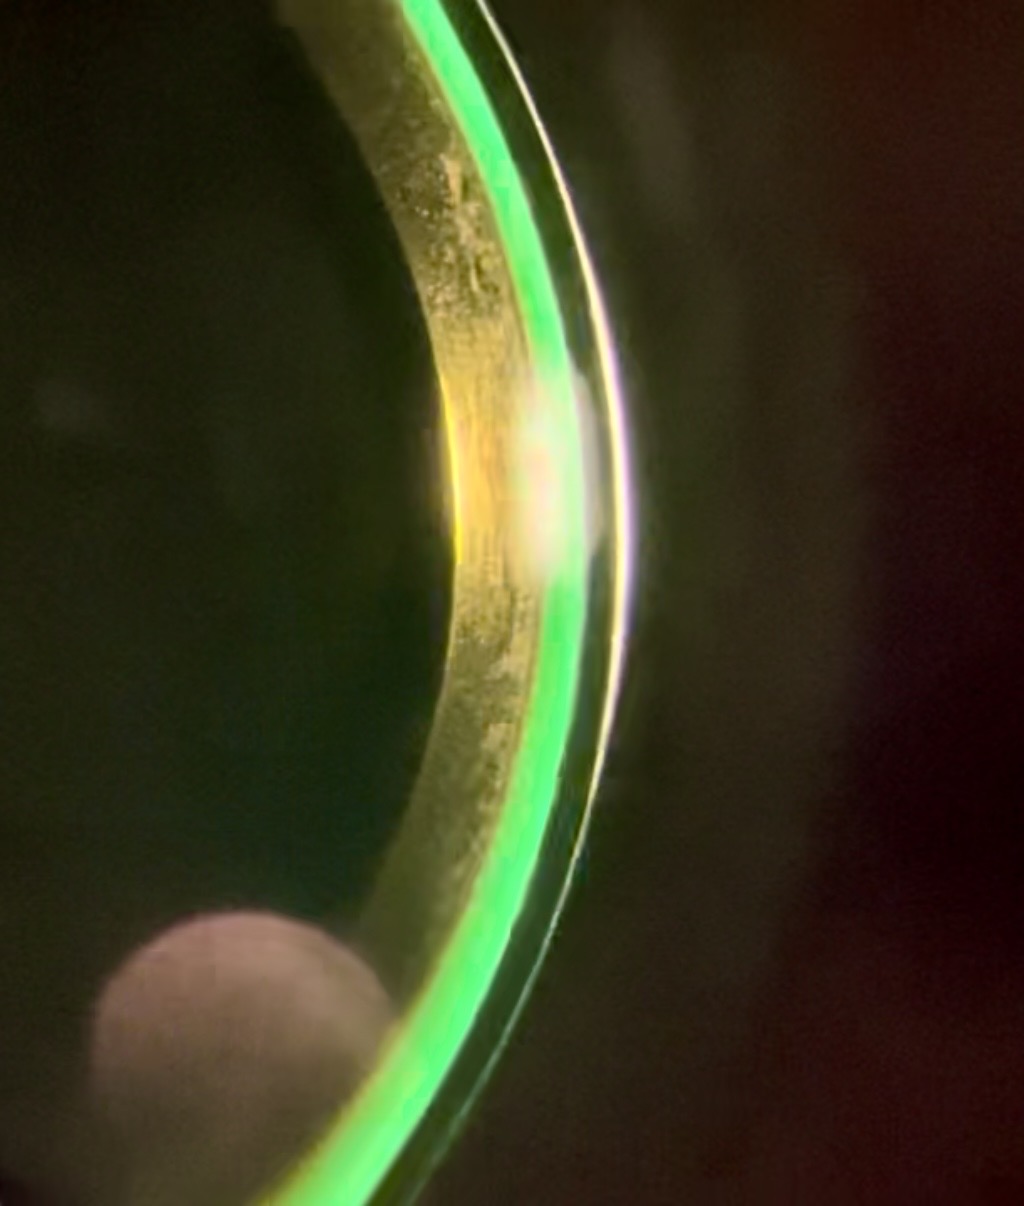

Custom scleral lenses are designed to vault over the irregular cornea and create a smooth optical surface, allowing light to focus properly again. The lens rests on the white part of the eye rather than the sensitive cornea, providing improved comfort and stable, clearer vision.

Custom scleral lenses vault over the cornea and create a smooth, stable optical surface, allowing light to focus properly for clearer and more consistent vision. Because the lens rests on the white part of the eye rather than the sensitive cornea, many patients also experience improved comfort and stability.

KERATOCONUS - Keratoconus is a progressive eye disease where the normally dome-shaped cornea thins and bulges into an irregular cone, distorting vision by scattering light, leading to blurry vision, halos, glare, and light sensitivity, often starting in the teens or early 20s and worsening over 10-20 years, with causes not fully understood but linked to genetics, allergies, and eye rubbing. Vision loss from Keratoconus can be fully restored with Scleral Lenses.